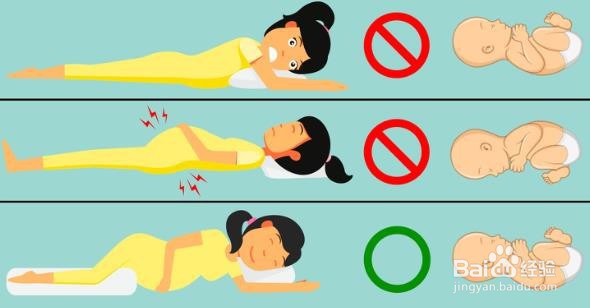

8、睡眠姿势:根据研究,孕妇最安全的睡姿是左侧睡。据专家介绍,孕妇在睡觉或运动时应避免仰卧。即使是在怀孕第28周仰卧的女性也可能增加死产的风险,因为这个位置限制了胎儿的血液和氧气供应。